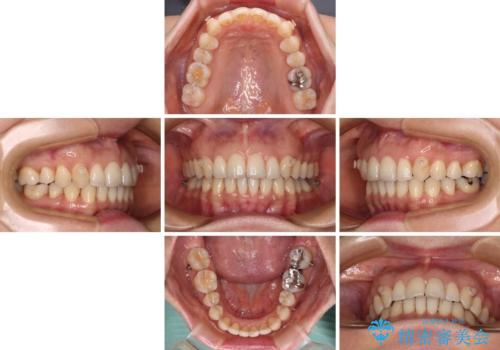

矯正治療の後戻り インビザライン・ライトによる矯正治療

- 矯正治療の後戻りを気にして来院された患者様です。

後戻りは軽微であったので、インビザライン・ライトにより矯正治療を行うこととしました。

インビザライン・ライトは提供されるマウスピースの数に制限があり、通常のタイプよりもマウスピース提供期間が短くなっている一方、安価に治療を行うことができるプランです。

治療のゴールも変更できないため、軽微な歯列不正や、後戻り改善などに適しています。